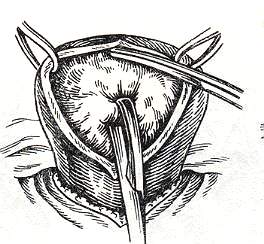

Современные методы лапаротомии и миомэктомии